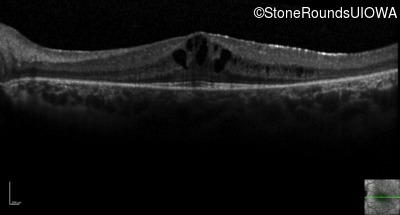

Optical Coherence Tomography - Left - 20/40 -1

Exemplar / OCT Stack